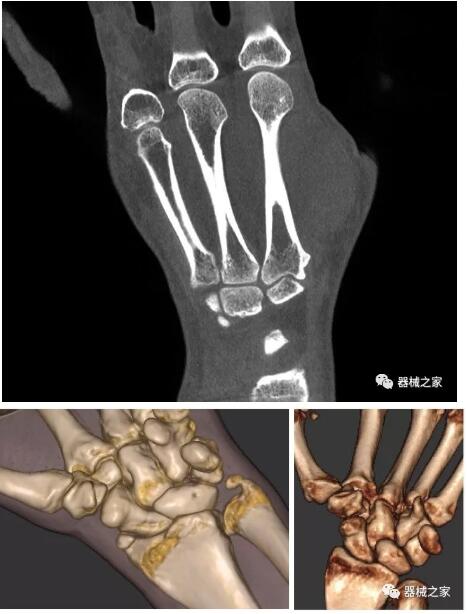

以下是這些“特立獨(dú)行”的CT所拍出來(lái)的圖像: